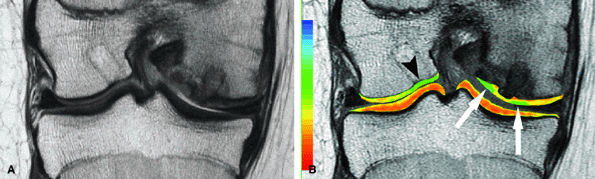

FIGURE 7.15 ● (A) Coronal fast spin-echo MR image of the knee in a 15-year-old girl with a previous partial meniscectomy demonstrates mild fibrillation of the cartilage overlying the lateral tibial plateau (arrow). (B) Corresponding quantitative T2 relaxation time map of the femorotibial articular cartilage coded to capture T2 values ranging from 0 to 100 msec demonstrates prolongation of T2 values over the plateau, but with unexpected prolongation over the lateral femoral condyle (arrowheads), which appeared normal on standard fast spin-echo cartilage-sensitive imaging. Green and blue reflect longer T2 values, yellow intermediate, and orange the shorter values.

|